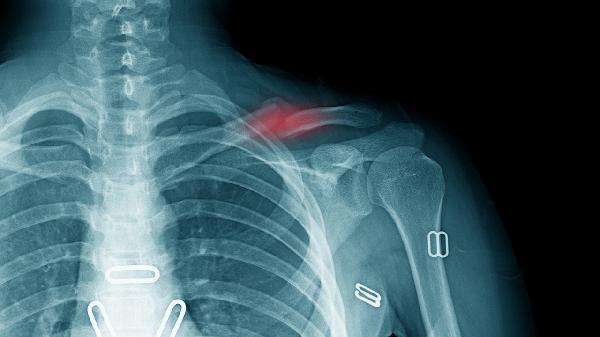

单纯线性骨折仅需简单固定,费用约2000-4000元;粉碎性骨折或伴有移位的骨折可能需多次手法复位,费用可达5000-8000元。儿童锁骨骨折愈合快,通常费用低于成人。